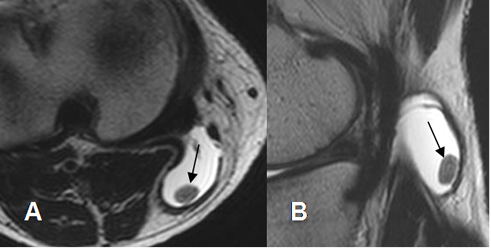

Fig 73. Condromatosis sinovial.

A: RM axial en T2 y B: RM sagital en T2. Cuerpo libre moderadamente calcificado, en el interior de un quiste de baker.